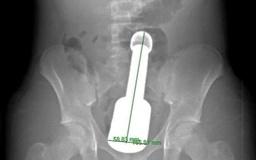

Nội soi, gắp chiếc chìa khóa cửa trong dạ dày bệnh nhi 14 tuổi

Bệnh nhi 14 tuổi ở Quảng Ngãi nhập viện vì nuốt một chiếc chìa khóa cửa. Các bác sĩ Bệnh viện Sản - Nhi tỉnh Quảng Ngãi đã nội soi can thiệp kịp thời, gắp dị vật an toàn, tránh biến chứng nguy hiểm.